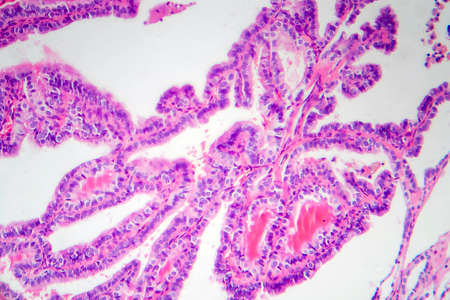

Papillary serous ovarian adenocarcinoma, cancer of ovary, light micrograph, photo under microscope